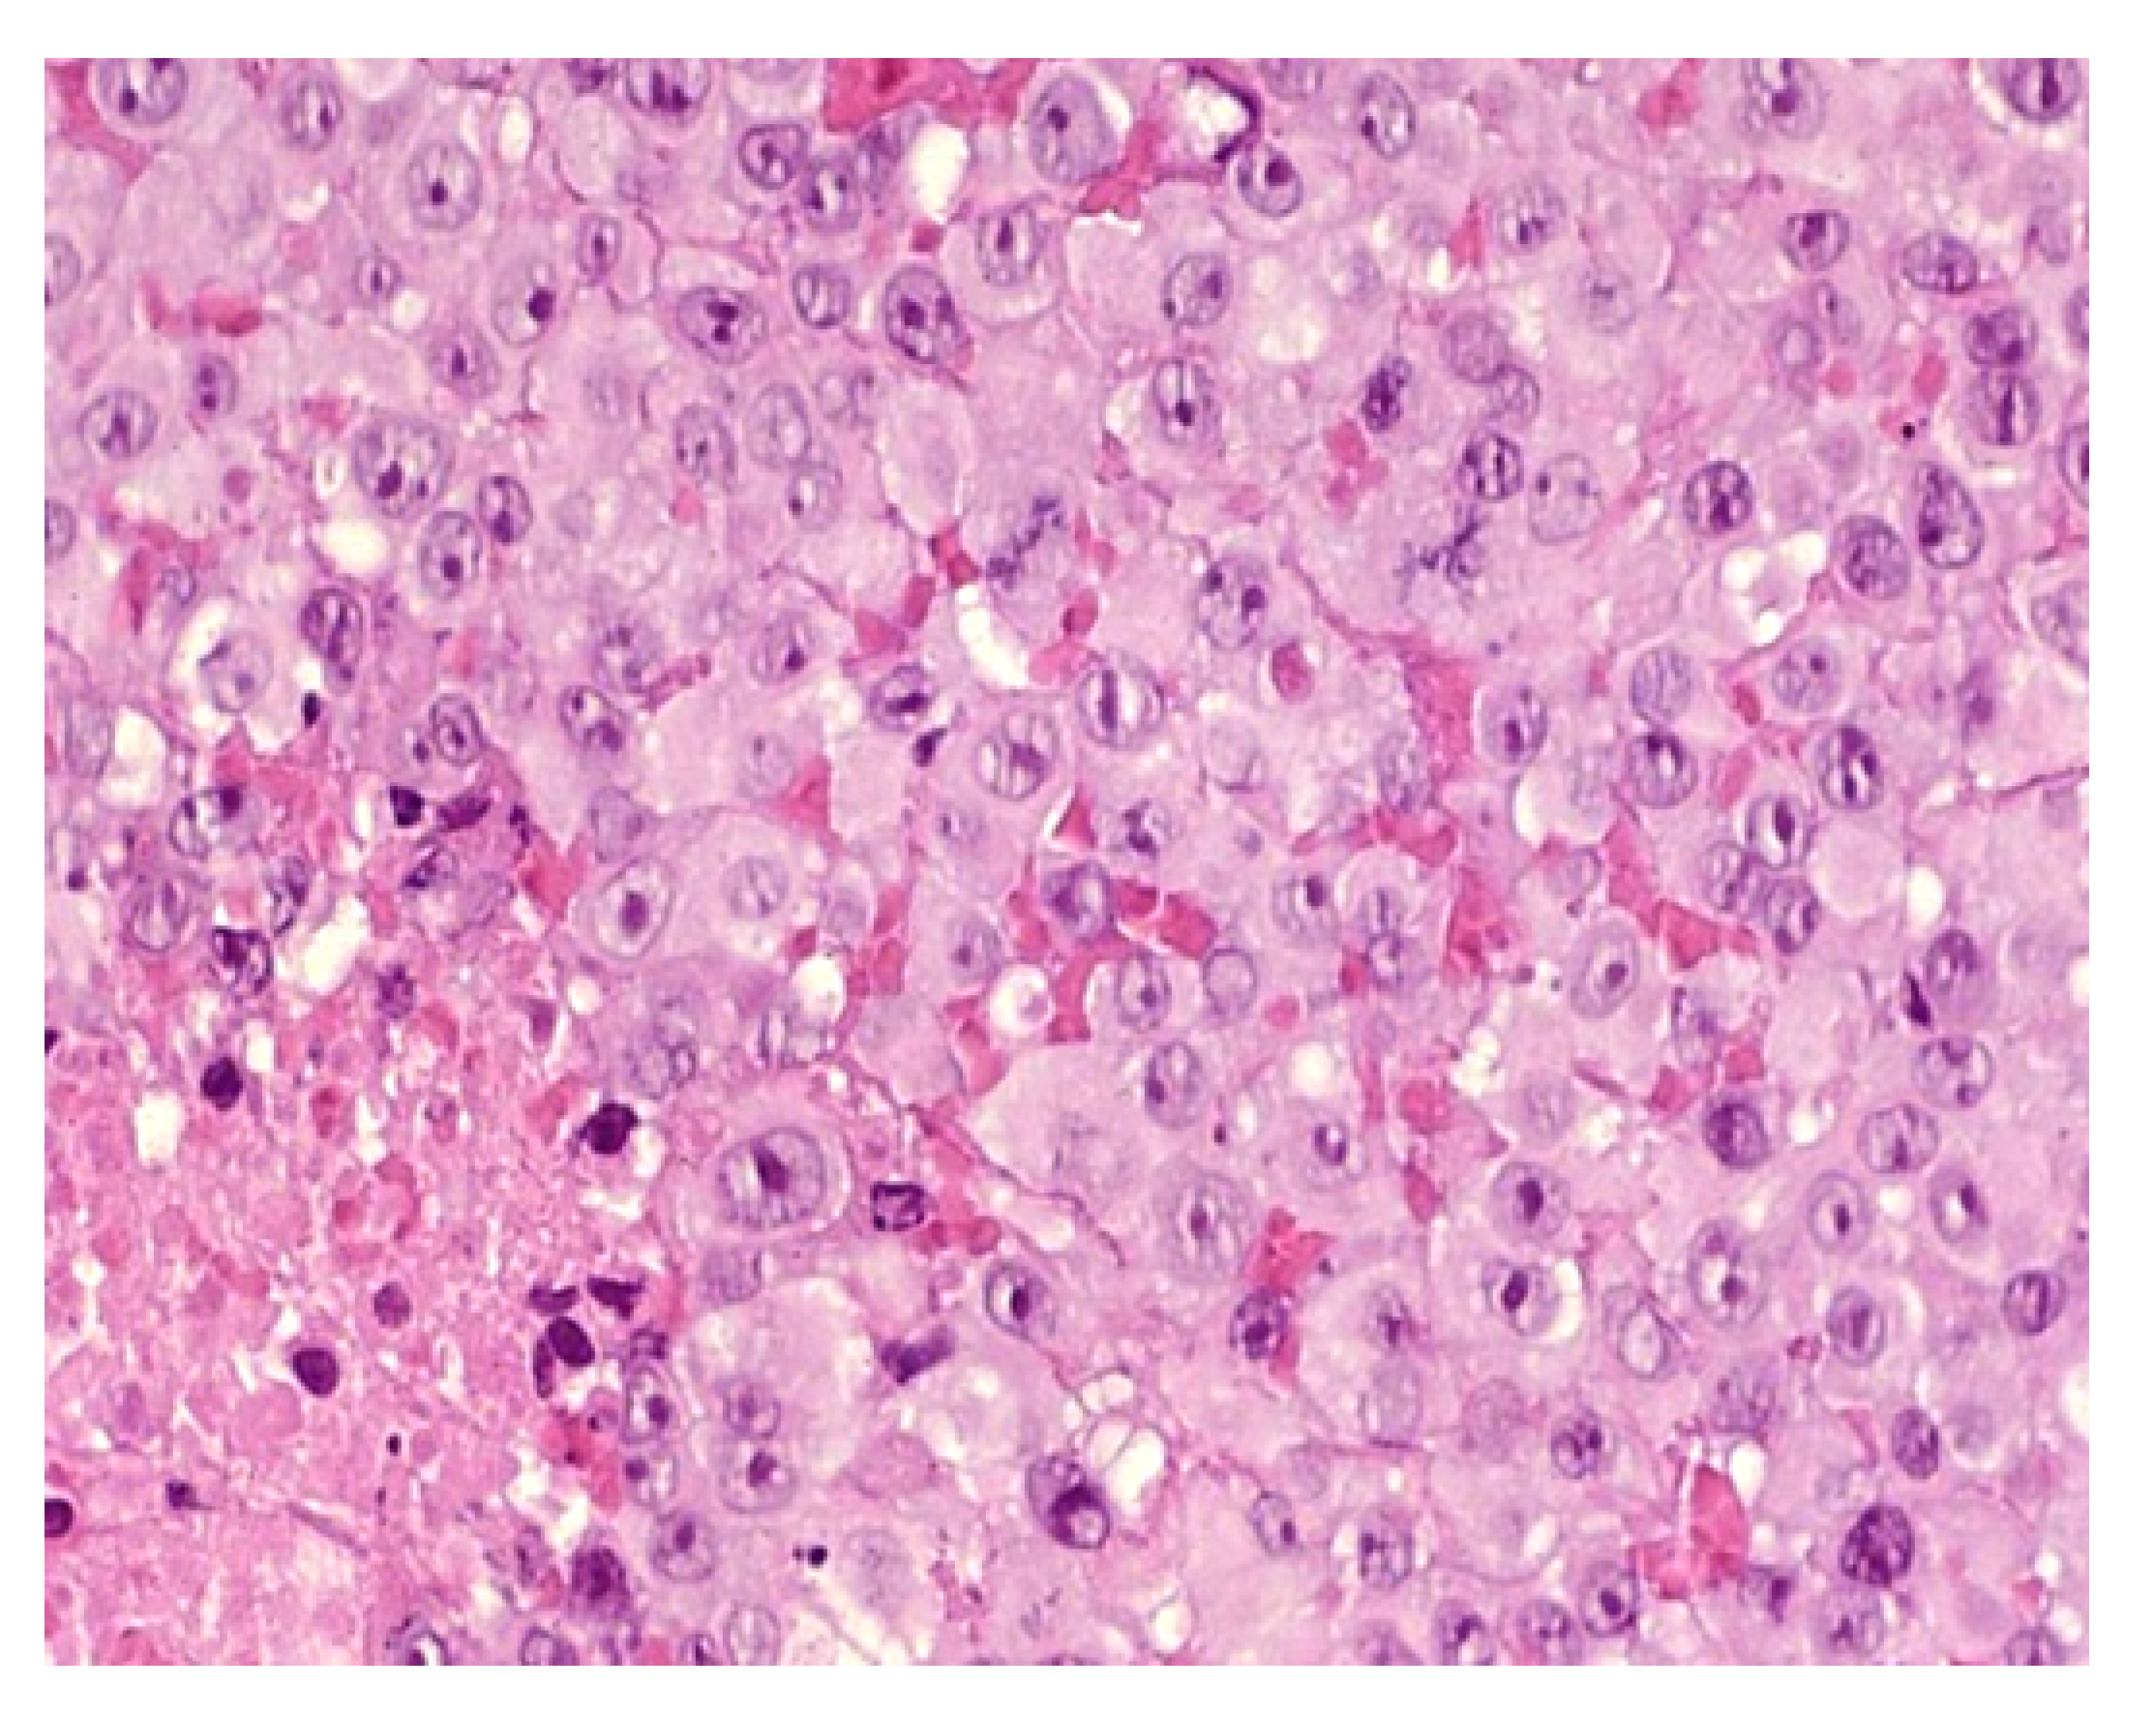

Figure 4.

Congenital leukemia cutis: (a) blueberry muffin rash; (b) 4× dense dermal infiltration separated from the epidermis by a grenz-zone; (c) 10× medium-sized blastic cells arranged in single-file between collagen bundles and with a peri-vascular and peri-adnexal arrangement as well; (d) 25× apoptotic cells and mitotic figures; (e) CD68 intense positivity; (f) Ki67 immunostaining: almost 100% of nuclei are positive.

Histology

In most cases, the diagnosis is straightforward. A dense dermal infiltrate is separated from the epidermis by a “grenz zone” and extends into the subcutaneous tissue with a peri-vascular and peri-appendageal arrangement. Cells are arranged in single file between the collagen bundles. They are medium-sized, with a high nuclear-cytoplasmic ratio, nuclear debris (apoptosis), and mitotic figures (Figure 4b–h). A good clue is the very high proportion of tumor cells, and almost no reactive inflammatory cells, in the infiltrate. CD68, lysozyme, and myeloperoxidase are the most sensitive immunohistochemical markers for detecting monoblasts (acute monocytic leukemia 5) or myelomonoblasts (acute monocytic leukemia 4), which account for the vast majority of leukemias at this age. In most cases, 90 to 100% of the cells are positive for KI67. Importantly, these immature monoblasts may lack CD163.